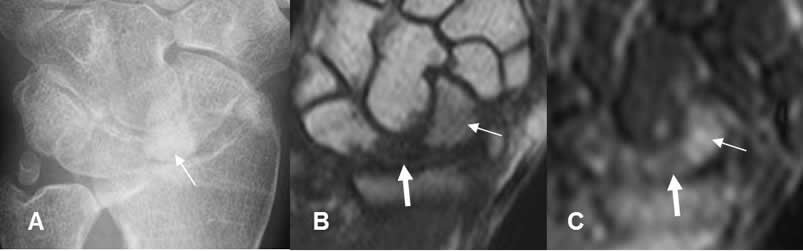

Fig 132. Osteonecrosis del escafoides.

A: Rx AP, B: TAC reconstrucción coronal y C: TAC reconstrucción sagital. Fractura del escafoides fijada con material de osteosíntesis. El polo inferior es denso y ha perdido volumen, por osteonecrosis. (Flechas gruesas). Adicionalmente hay signos de seudoartrosis, con aumento del espacio entre los extremos, esclerosis de los bordes y ausencia de callo óseo. (Flecha delgada).